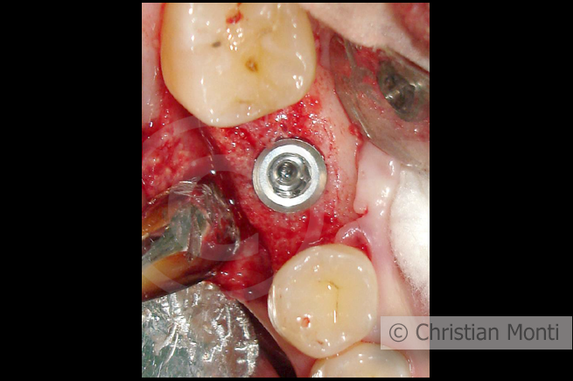

EDENTULIA SINGOLA

Impianto dilazionato in sostituzione di un molare inferiore